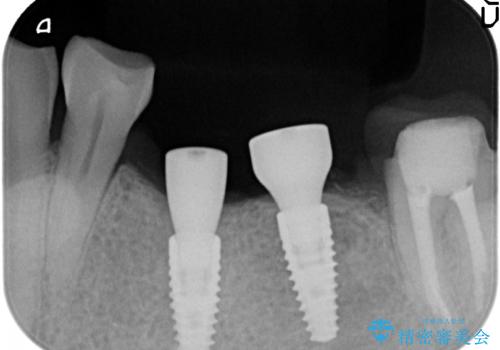

- 左下奥歯が虫歯で抜歯になってしまったため、インプラントにしたいといらっしゃった方の症例です。

欠損部位である左下5、6番目にインプラントを埋入し、オールセラミッククラウンによる補綴を行いました。

左下7番目は再根管治療を行い、オールセラミッククラウンによる補綴を行いました。

- オールセラミッククラウン…¥100,000×3、仮歯…¥10,000×3、インプラント(ストローマン)…¥200,000×2、カスタムアバット…¥100,000×2、ファイバーコア…¥20,000、根管治療費別途費用は治療当時の料金となります